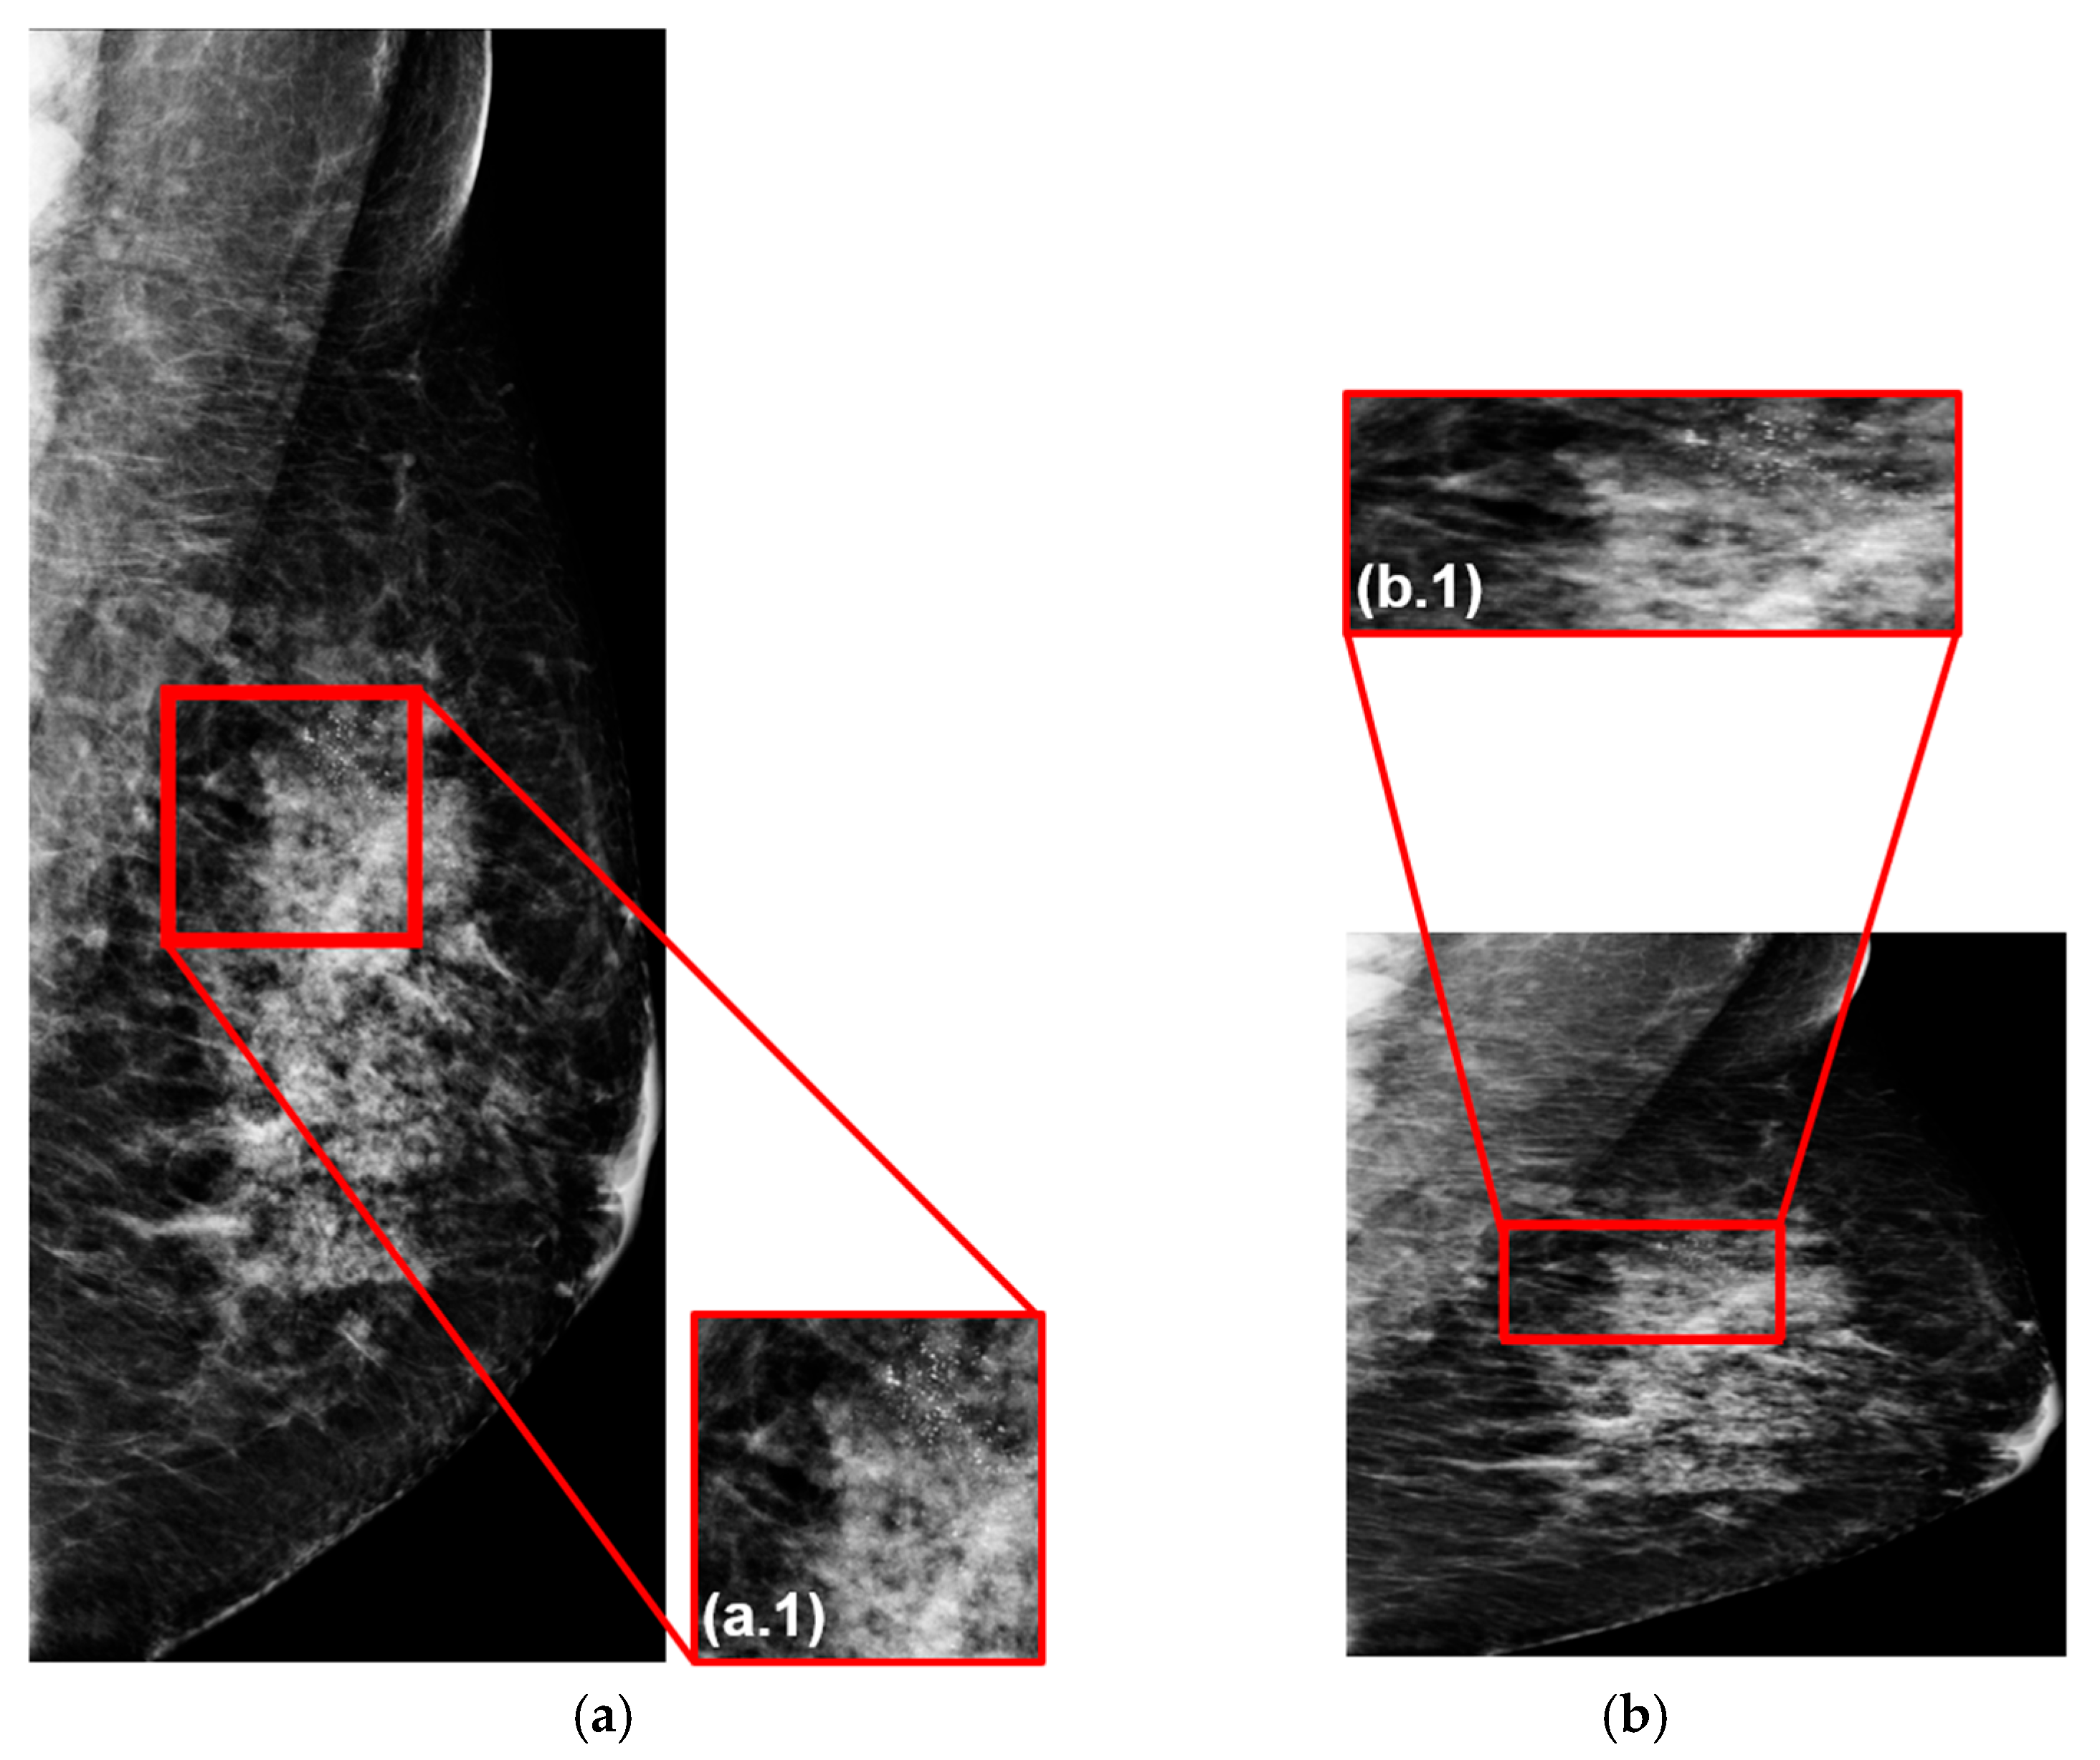

3.3.1. Image Resizing and Fidelity Preservation

3.3.2. Image Augmentation